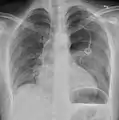

الأشعة السينية على الصدر

عادة ما يكون التصوير الشعاعي العادي للصدر، بإشعاع الأشعة السينية من الخلف (من الخلف للأمام) هو أنسب فحص في البداية. وعادة ما يتم تنفيذ ذلك خلال الشهيق (مع كتم النَفَس). لأن التصوير بالأشعة السينية أثناء الزفير (بعد خروج الهواء) لا يعطي أي معلومات إضافية.[12][13] إذا لم تُظهر الأشعة السينية الساقطة من الخلف للأمام استرواح صدري، ولكن كان هناك شكوك قوية في وجوده، يتم عمل أشعة سينية جانبية ( بإسقاط الأشعة من الجانب)، ولكن هذه ليست الطريقة الروتينية.[13][17] ومن المألوف وجود انحراف المنصف (التركيب بين الرئتين التي يحتوي على القلب، والأوعية الدموية الكبيرة، والممرات الهوائية الكبيرة) بعيدا عن الرئة المتضررة بسبب اختلافات الضغط. لذا فإن هذا الانحراف ليس دليلا على حدوث استرواح الصدر الضاغط، إنما يتحدد أساسا عن طريق مجموعة من الأعراض بالإضافة إلى نقص الأكسجين، والصدمة.[12]

ليس كل استرواح صدري مثل الآخر، فقد لا يشكل بعضها سوى تجويف من الهواء في مكان معين في الصدر فقط.[13] كما يمكن ملاحظة كميات صغيرة من السوائل في الأشعة السينية على الصدر (استرواح الصدر الموهي)، وقد يكون هذا السائل دم.[12] في بعض الحالات، قد يكون الشيء الوحيد غير الطبيعي في الأشعة هو "علامة التلم العميق"، التي تظهر فيها المساحة الصغيرة الموجودة عادة بين جدار الصدر والحجاب الحاجز كبيرة بسبب الوجود غير الطبيعي للسوائل.[14]